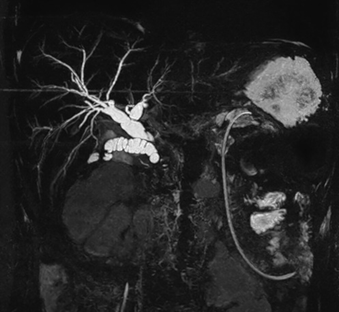

MRCP 3D Scanning in Dhaka at Unico Hospitals: Clear Results in Just 15 Seconds

Unico Hospitals takes pride in offering MRCP 3D scanning technology that cuts scan time to just 15 seconds. Patients experience sharper images, safe noninvasive procedures, and excellent care from skilled professionals using the best equipment available.

Unico Hospitals stands apart from other medical centers with our advanced MRCP technology. We combine speed, precision, and comfort to give you the best possible imaging experience. Our 3T system delivers results in just 15 seconds while keeping you comfortable throughout the process. Five key features make our MRCP service the top choice for patients and doctors alike.

Unico's MRCP technology captures complete 3D images in just 15 seconds. Traditional MRCP scans take 30-45 minutes, but our advanced system cuts this time dramatically. You spend minimal time in the scanner while getting the same detailed results.

Our 3T (3 Tesla) magnetic field strength delivers images that surpass standard MRI machines. This powerful technology produces sharper, clearer pictures of your bile ducts and pancreas. Doctors can spot problems that weaker machines might miss completely.

The stronger magnetic field creates better contrast between different types of tissue. Your radiologist can see tiny details in your pancreatic ducts and bile system. This improved clarity leads to more accurate diagnoses and better treatment planning. You get the most advanced imaging technology available without needing multiple scans or repeat visits.

Our MRCP system excels at more than just bile duct imaging. The versatile technology supports multiple body imaging applications beyond standard MRCP scans. Advanced imaging techniques give doctors detailed 3D views of complex anatomical structures.

This versatility means you can get multiple types of scans during one visit if needed. The system's flexibility helps doctors choose the best imaging approach for your specific condition. Detailed 3D reconstruction lets radiologists examine your organs from every angle. You benefit from having access to multiple imaging options without visiting different facilities or scheduling separate appointments.